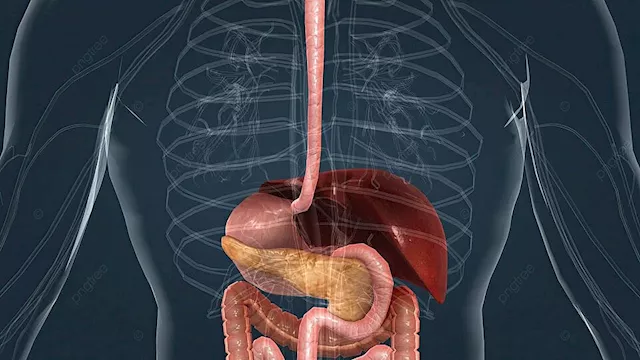

صحة الأمعاء تؤثر بشكل مباشر على صحة الجسم ككل، من الهضم إلى تعزيز المناعة وتحسين المزاج. متابعة العلامات اليومية في الجسم يمكن أن يساعد في رصد أي خلل مبكراً والحفاظ على جهاز هضمي صحي ومتوازن.

التقييم اليومي لصحة الأمعاء

كيف تعرف أن حركة أمعائك طبيعية؟

هل الانتفاخ والغازات بعد الأكل أمر طبيعي؟

هل نظامك الغذائي يدعم صحة أمعائك؟

هل تؤثر الأمعاء على مزاجك وبشرتك؟

هل يجب القلق من تغيرات الشهية أو الوزن؟